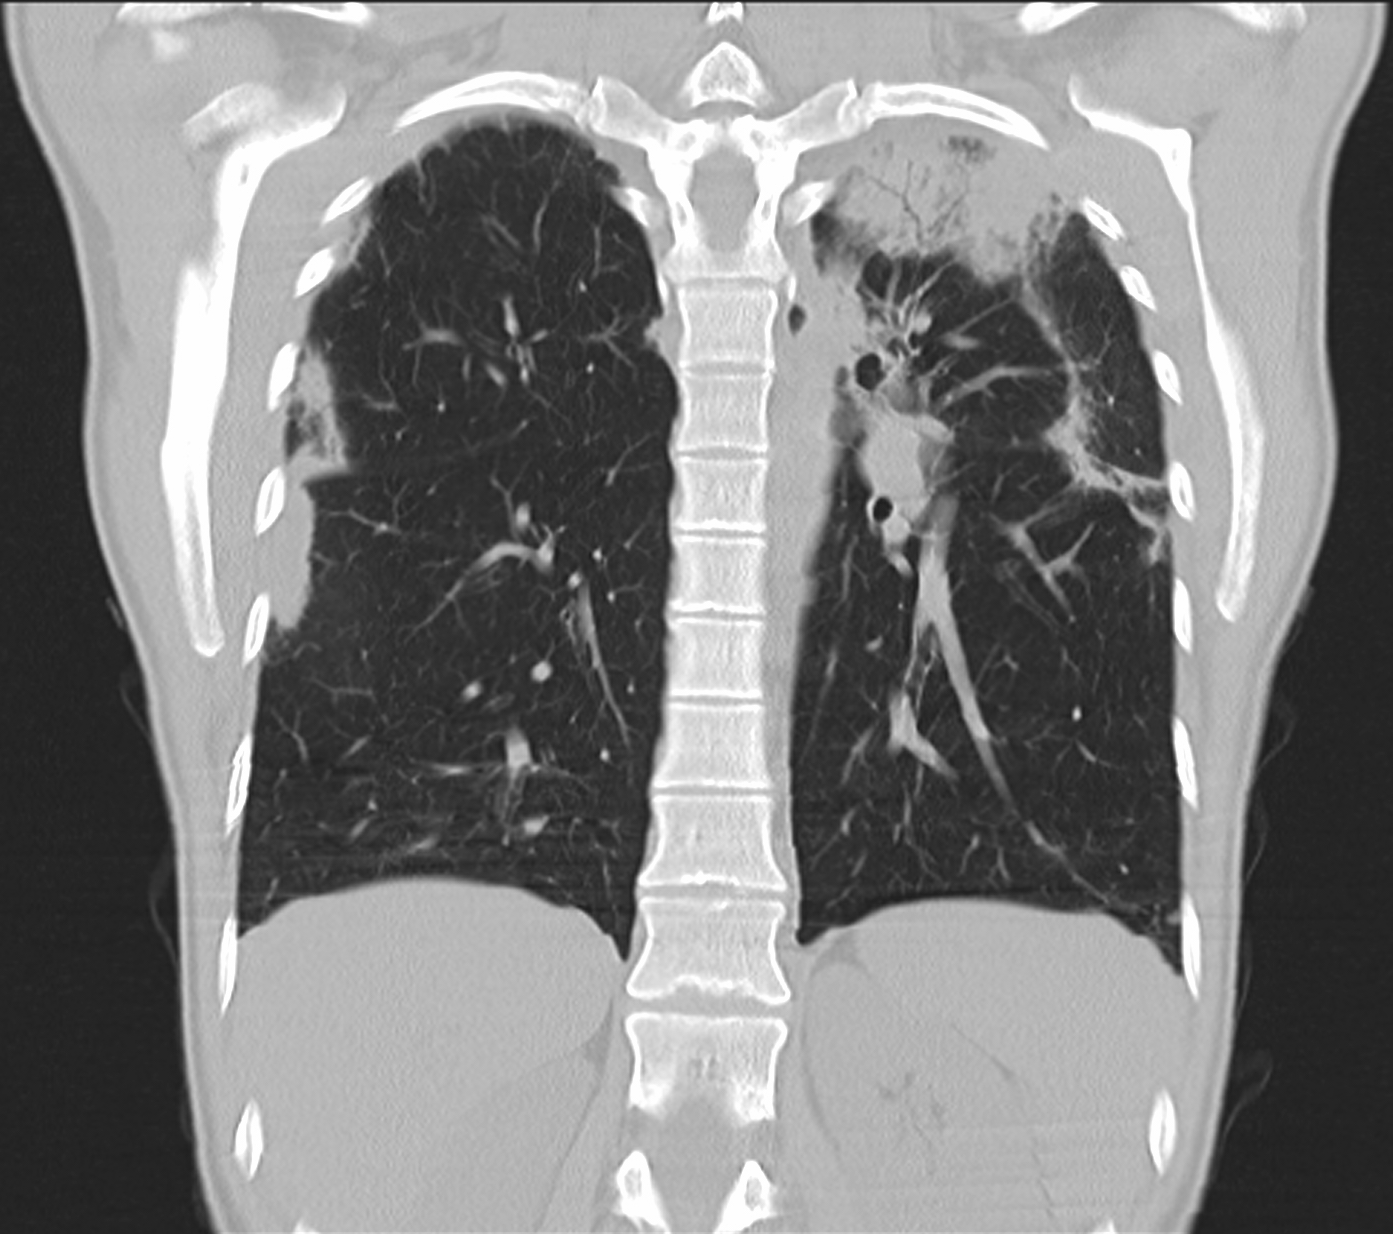

26. ARDS, CT, coronary reconstruction

52 year old woman, dyspnea, septic shock.

Bilateral opacity according to rough, diffuse interstitial edema, irregular atelectasis and bronchogram in the basal segments